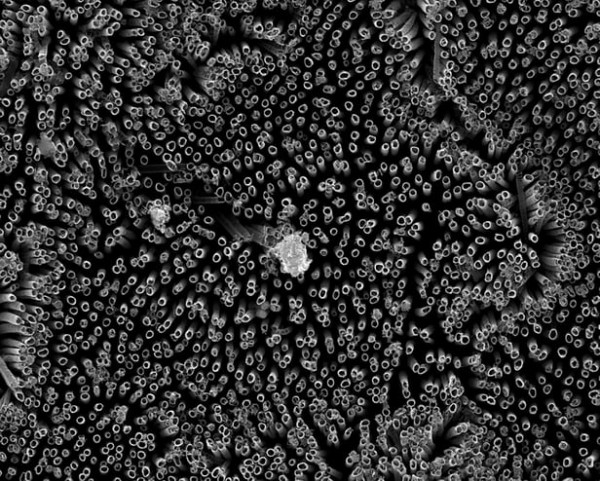

具體來說, 科學家Arun Kota和Ketul Popat 在鈦片上培養了一種超級疏血(superhemophobic – blood)的「表面」。研究人員在實驗室測試中對不同類型的「表面」進行了測試, 並發現氟化納米管的表面紋理和化學性質能產生最低水準的血小板粘附。

Kota表示:「我們正在使用一種血液『不喜歡』接觸的材料。」Popat補充說:「如果我們可以設計出血液幾乎不接觸的材料,那麼將幾乎沒有形成凝塊的可能性,這是一系列協調的事件。在這裡,我們的目標是預防第一組事件。」